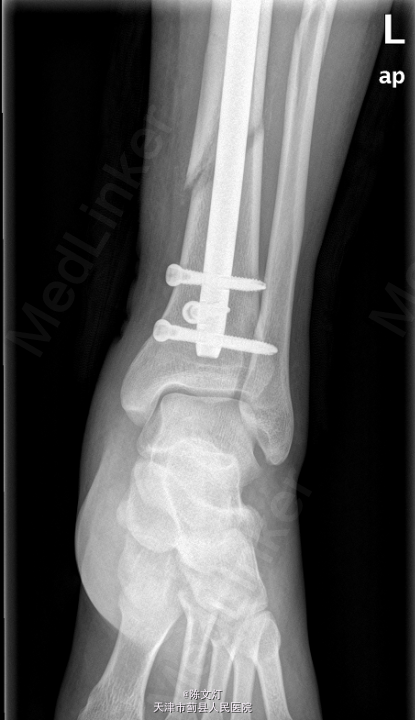

左胫腓骨骨折 全麻下行行左胫骨骨折闭合复位内固定术,术后予盐酸头孢替安2.0g 静滴bid预防感染。

左下肢切口处敷料包扎固定妥,切口对合良好。出院后注意休息,避免左腿负重,避免剧烈活动,防止二次损伤。